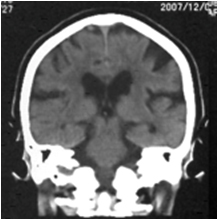

特発生正常圧水頭症のCT画像

特発生正常圧水頭症の特徴的CT所見(通常は脳を水平に撮影しますが、冠状に撮影した画像のほうがより特徴を捉えることができます)